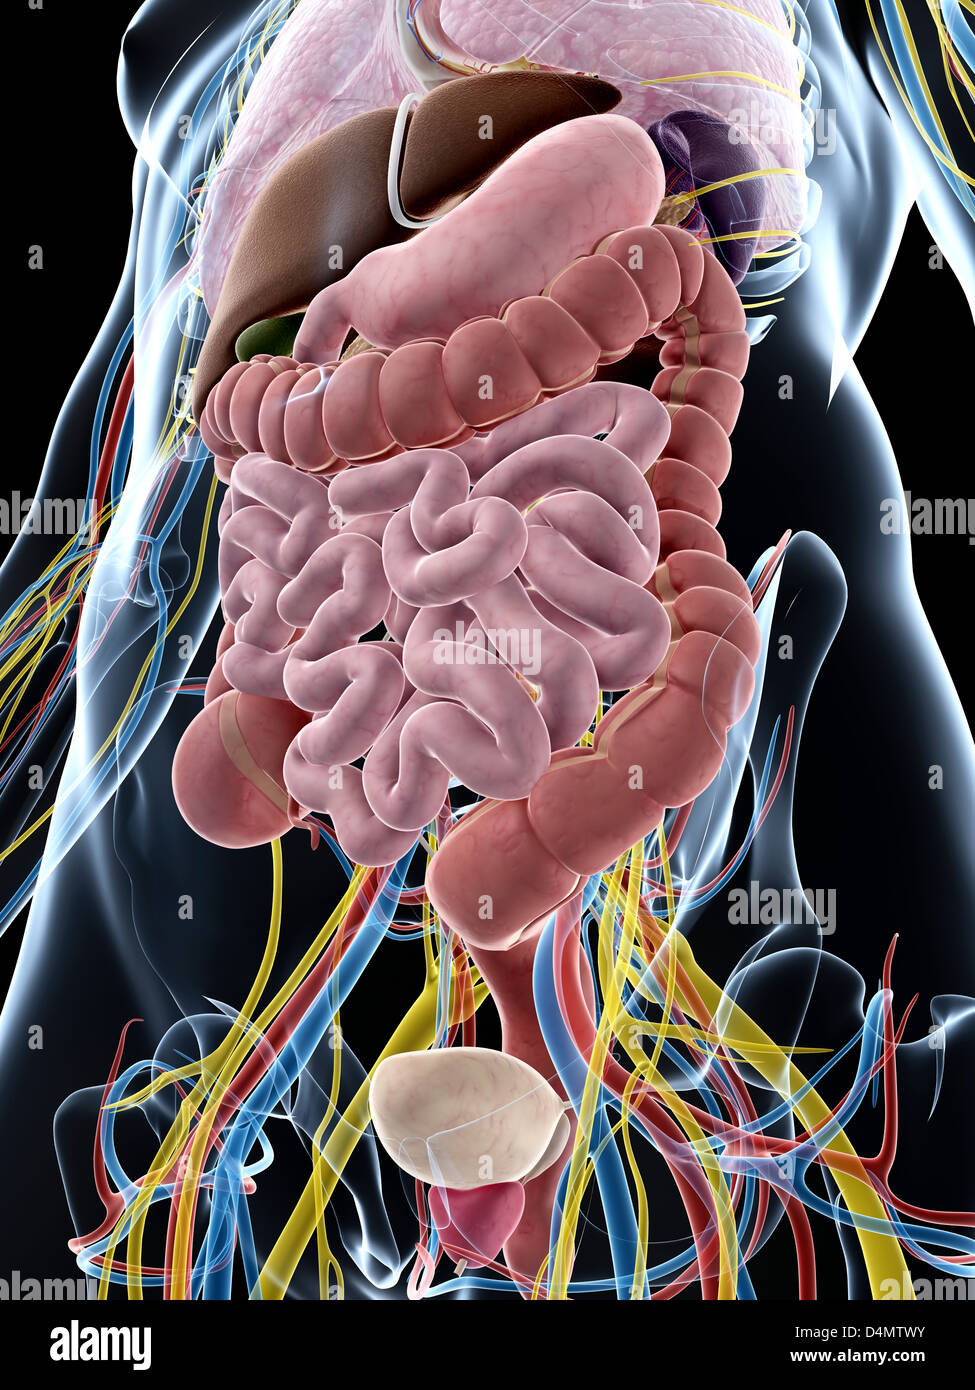

RFDGYRD7–Männliche Anatomie, inneren Organe allein, volle Atmungs- und Verdauungssystem, mit einigen Organen Cutaway. Anatomie-Bild.

RF2GB8D4J–3D-Darstellung des Verdauungssystems der männlichen Anatomie, zusammen mit anderen inneren Organen. Glasbild auf blauem Hintergrund, Vorderansicht.